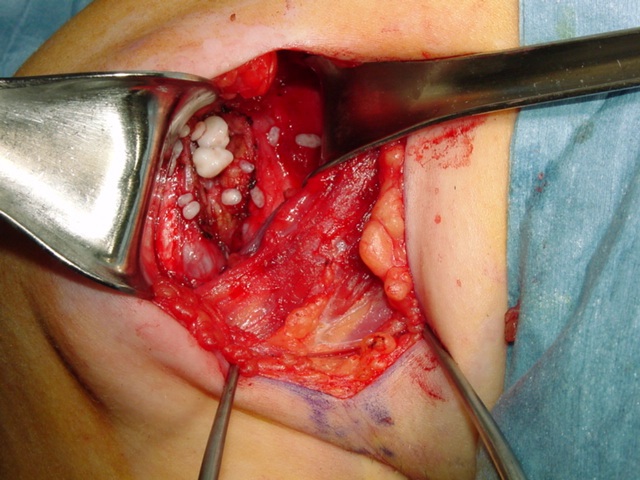

The treatment for synovial chondromatosis is the excision of the involved synovium and removal of the cartilage nodules (Fig. 6, Fig. 10-11). Recurrence is infrequent although it may recur in cases where removal is incomplete or synovium is affected diffusely. Malignant transformation is seen in less than 5% of the cases and is usually a low grade malignancy (synovial chondrosarcoma). Some papers suggest that degenerative arthritic changes still progress in the involved joint after surgical removal. In other words surgical removal may not prevent development of arthritis in the affected joint.

Fig 10 & 11. Intra-operative photographs demonstrate nodules of cartilage in the right shoulder joint (Fig. 10) and resection of the synovium (Fig. 11).